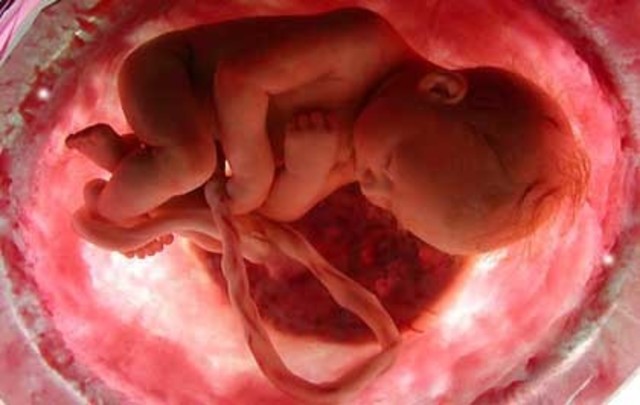

• 36a SEMANA-OCTAVO MES

36a SEMANA-OCTAVO MES

Al final del 8º mes el bebé mide 45cm y pesa entre 2200 y 2500 gramos. El cabello es más largo y grueso. La piel pierde totalmente el lanugo.

• 38a SEMANA-NOVENO MES

38a SEMANA-NOVENO MES

El feto mide 50 cm, la piel conserva la vernix caseosa. El feto ya alcanzó la madurez pulmonar que le permitirá respirar cuando salga del útero materno, lo mismo ocurre con todo su organismo. El bebé ya está preparado para el parto, hecho que le permitirá iniciar el vínculo con su madre fuera del vientre materno.